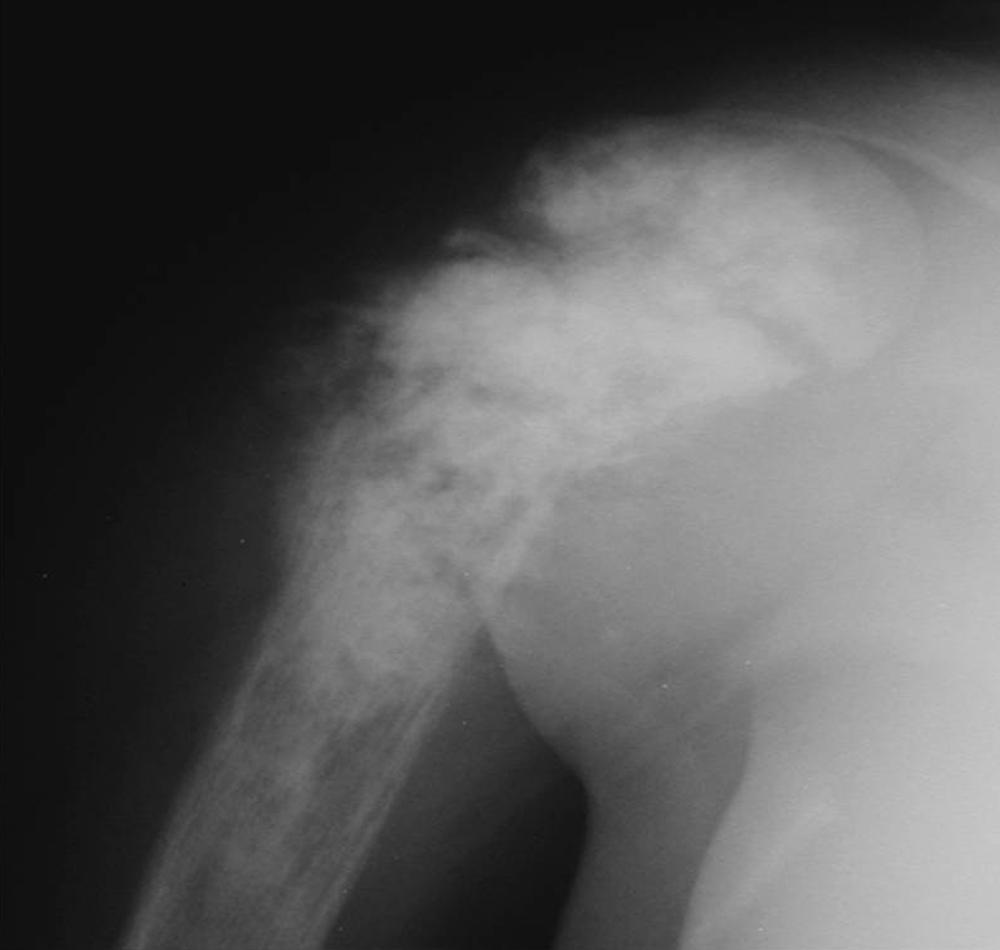

FIGURE 24.5, Stage IA malignant lesion: chondrosarcoma of the proximal femur.

FIGURE 24.6, Stage IIB malignant lesion: osteosarcoma of the proximal humerus.